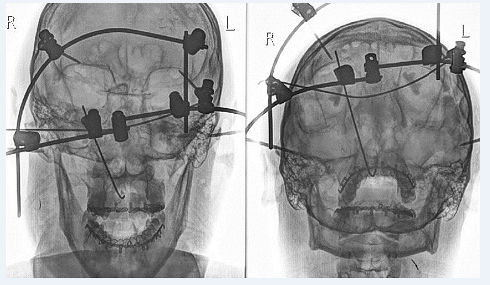

На рис. 1, 2 представлен внешний вид и контрольная рентгенограмма пострадавшего после малоинвазивного остеосинтеза.

Рис. 1. Внешний вид пострадавшего И. после операции

К тяжёлым повреждениям ЧЛО средней зоны лица относятся переломы верхней челюсти по верхнему (черепно-лицевые разъединения) и по среднему типу. При таких переломах основной задачей хирурга является фиксация лицевого скелета к мозговому минимально инвазивным способом. Репозиция и фиксация отломков осуществляется внеочаговыми методами. Хорошо зарекомендовал себя при данных повреждениях малоинвазивный внеочаговый остеосинтез по методике Д.Ю. Мадай [7, 8] (рис. 1).

Рис. 2. Контрольная рентгенограмма пострадавшего И. после операции